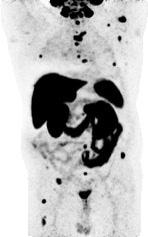

· PSMA-PET: Acetabulum-Met.

· Ossärer Progress (LWK 1)

· Metastasen: Femur & Oberarm

→ High-Volume mHSPC

Radiologisch: Komplette Remission ossärer Metastasen